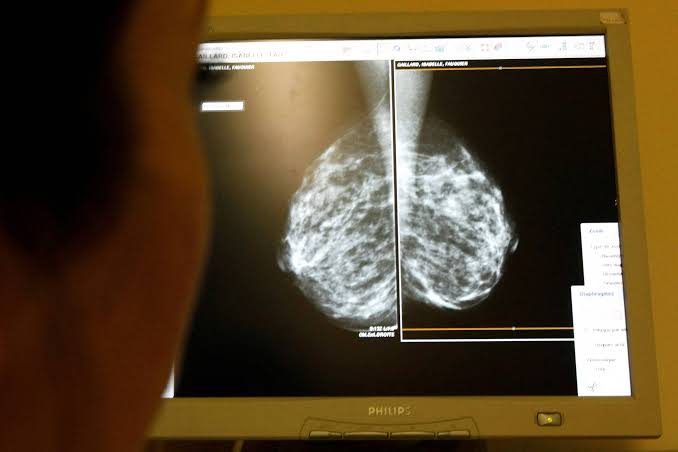

Além disso, uma organização médica independente recomendou que as mulheres comecem a realizar mamografias a partir dos 40 anos, em vez dos 50, e que esses exames sejam feitos a cada dois anos.